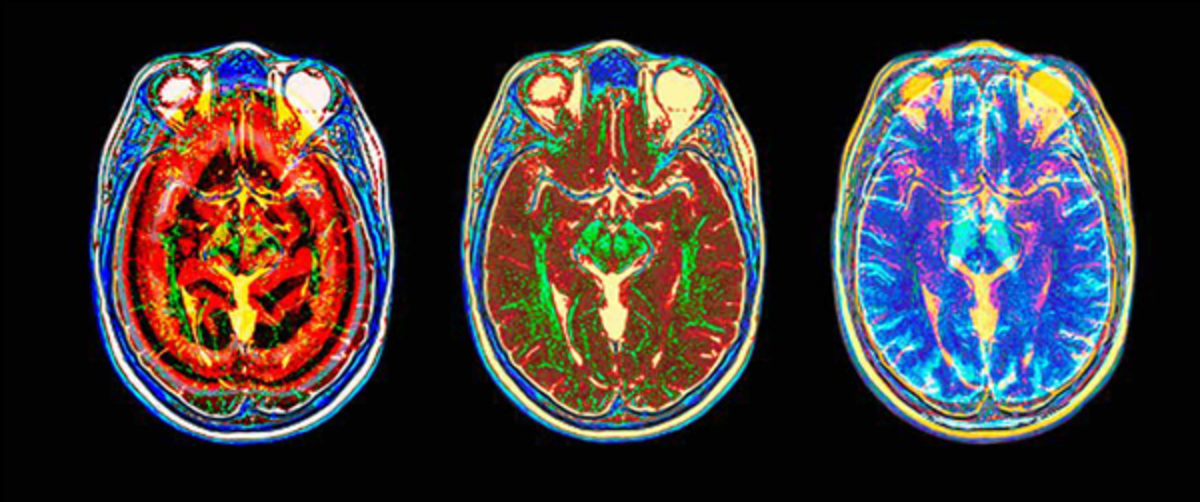

Παρά τις δυσκολίες της συγκεκριμένης περίπτωσης, καθώς ο όγκος βρισκόταν σε πολύ κρίσιμη περιοχή, με τον υπερσύγχρονο εξοπλισμό της Ευρωκλινικής Αθηνών, το άριστα εκπαιδευμένο προσωπικό του χειρουργείου και της Μονάδας Εντατικής Θεραπείας, καθώς και την έμπειρη χειρουργική ομάδα, η επέμβαση, διάρκειας 10 ωρών, ολοκληρώθηκε με εξαιρετική επιτυχία και η μετεγχειρητική μαγνητική τομογραφία έδειξε πως ο όγκος αφαιρέθηκε σχεδόν στο σύνολό του.